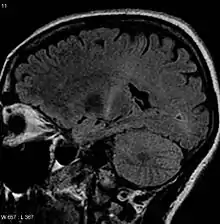

An MRI of the brain (axial FLAIR) looking at a person as if from above that shows increased T2 signal as a small white region within the posterior part of the internal capsule around the center of the image, consistent with the diagnosis of ALS

An MRI of the brain looking at a person from side-on that shows increased T2 signal as a white region in the posterior part of the internal capsule that can be tracked to the motor cortex, consistent with the diagnosis of ALS